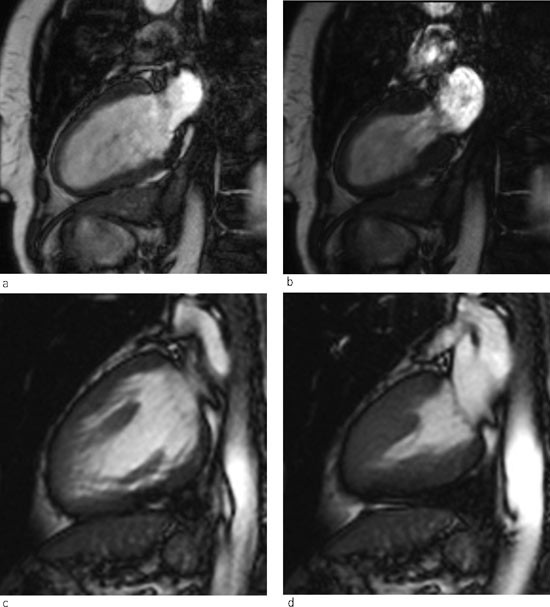

Pasienten ble observert i hjerteovervåkingen ved Ullevål universitetssykehus døgnet etter angiografien og behandlet for ytterligere forverring av hjertesvikten med bl.a. kontinuerlig overtrykk (continuous positive airway pressure, CPAP). NT-proBNP var forhøyet til 1 283 pmol/l. Dag 3 bedret tilstanden seg betydelig. MR-undersøkelse av hjertet viste fortsatt en viss apikal ballonering, men ejeksjonsfraksjonen hadde steget til 43 % (fig 2). Ny transtorakal ekkokardiografi senere samme dag viste kun lett hypokinesi apikoseptalt, og ejeksjonsfraksjonen ble estimert til 47 %.

Takotsubokardiomyopati ble første gang beskrevet i Japan (4). Først de siste årene er man blitt oppmerksom på tilstanden også i vestlige land (5). Syndromet er tidligere omtalt i Tidsskriftet (6). Takotsubo er den japanske betegnelsen på en krukke som benyttes til blekksprutfangst, og krukkens form illustrerer venstre ventrikkels kontraktilitetsmønster i akuttfasen (fig 4). I engelskspråklig litteratur er betegnelser som «left ventricular apical ballooning syndrome», «stress-induced cardiomyopathy» og «broken heart syndrome» også blitt brukt.